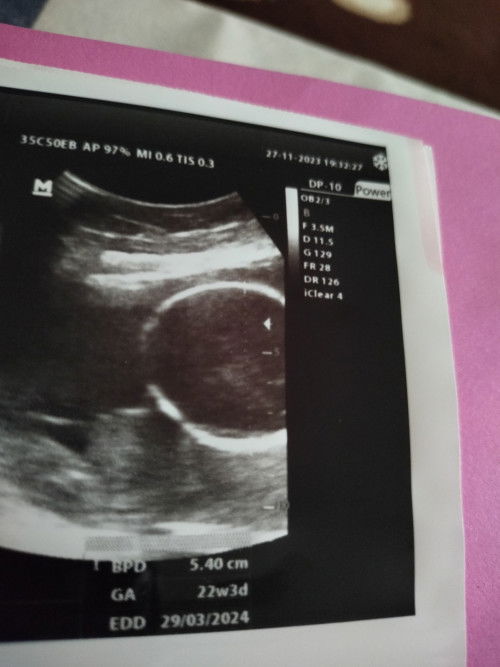

Mau tanya bunda bunda semua.. sdh saya cari juga istilah dalam USG knp yg ada cmn BPD, GA, sama EDD

#seriusnanya #bantusharing anak pertama bund,, pengen tau berat badannya juga bun, diatas tdk ada istilahnya saya liat